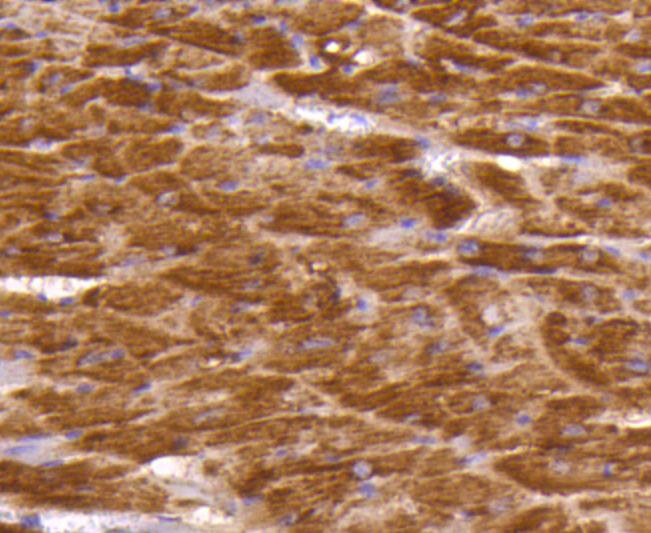

Immunohistochemical analysis of formalin-fixed, paraffin-embedded mouse heart tissue labeling Dopey-2. Counterstained with Hematoxylin.